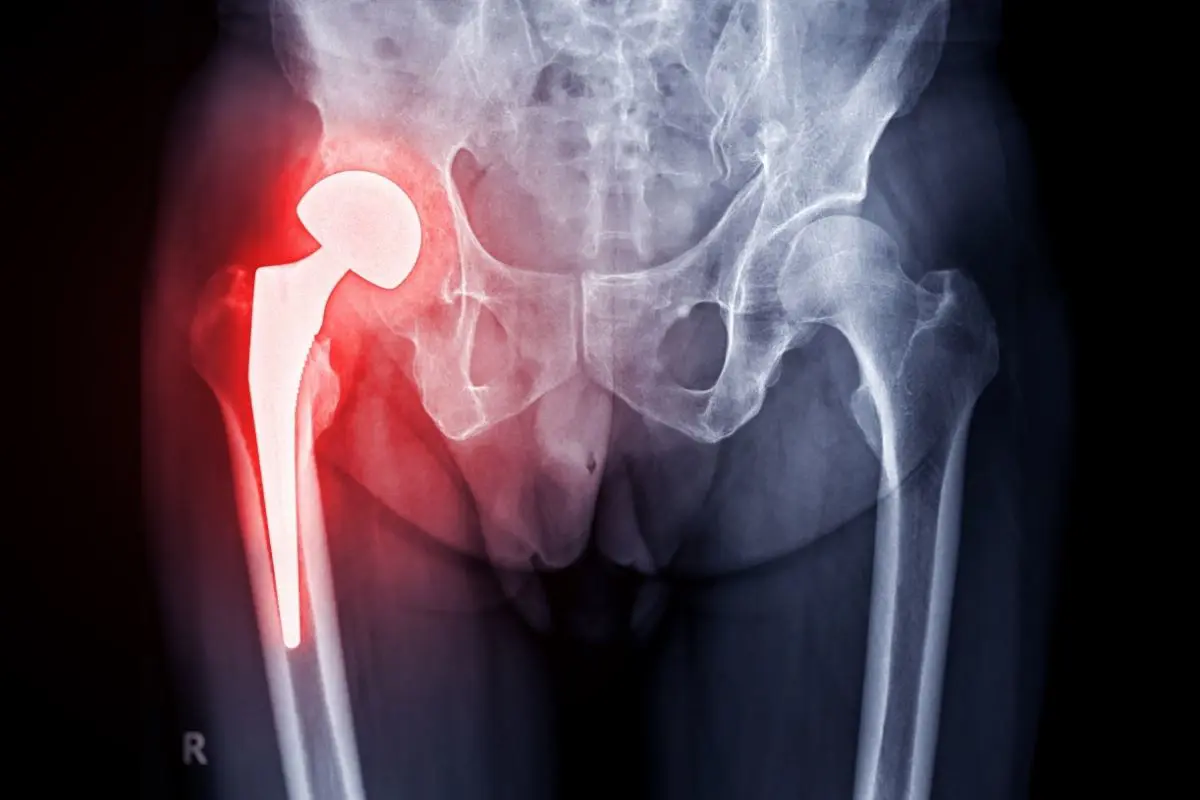

Hip replacement surgery, also known as total hip arthroplasty, involves replacing a damaged hip joint with an artificial implant designed to restore normal movement and reduce pain caused by conditions such as osteoarthritis, hip fractures, or joint degeneration. Modern surgical techniques, including minimally invasive approaches and high-quality prosthetic materials like titanium and ceramic implants, allow patients to recover faster and return to their normal routines with significantly improved quality of life.

During the surgery, the orthopedic surgeon removes the damaged parts of the hip joint and replaces them with a hip prosthesis made of durable materials such as titanium, ceramic, or medical-grade plastic. These artificial components are designed to replicate the natural movement of the hip, helping patients move more comfortably and with less pain.

The prosthetic hip usually consists of three main components:

- A metal stem placed inside the thigh bone (femur)

- A ball component that replaces the damaged femoral head

- A socket component that replaces the damaged hip socket

These components are made from durable materials such as titanium, ceramic, or medical-grade plastic, allowing the artificial joint to move smoothly and withstand years of use.